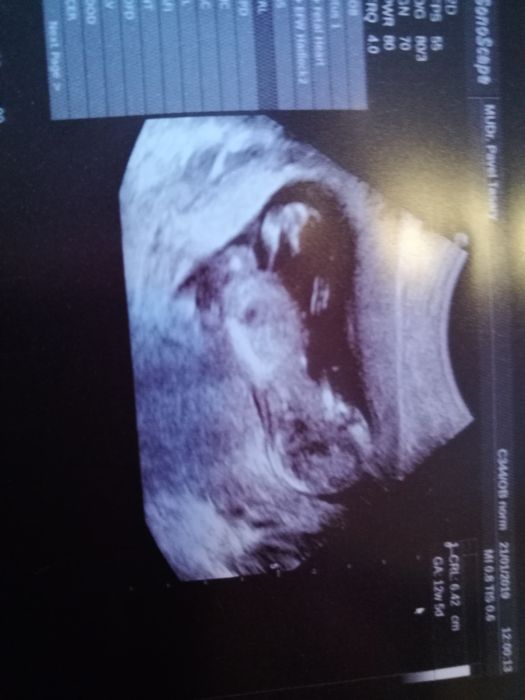

[1111899]GabiMu je tu nejak mrtvo no, ja jsem i na emiminu a tam je to zivejsi. Jinak jsem na tim stejne jako ty, je mi 33, 3 tehu a dnes 12+3 a zrovna sedim v cekarne na screening